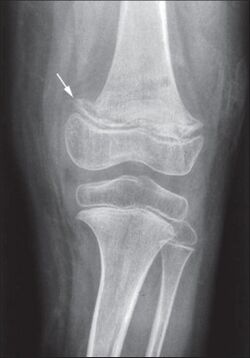

While many animals produce their own vitamin C, humans and a few others do not.[2] Vitamin C, an antioxidant, is required to make the building blocks for collagen, carnitine, and catecholamines, and assists the intestines in the absorption of iron from foods.[2][4][5] Diagnosis is typically based on outward appearance, X-rays, and improvement after treatment.[2]

Diagnosis is typically based on physical signs, X-rays, and improvement after treatment.[2]

Various childhood onset disorders can mimic the clinical and X-ray picture of scurvy such as: